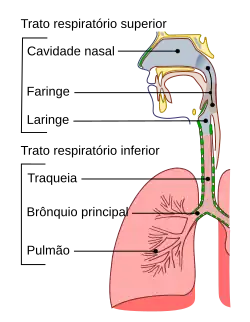

Constipação (português europeu) ou resfriado (português brasileiro) é uma doença infeciosa viral do trato respiratório superior.[7] Embora afete principalmente o nariz, pode também afetar a garganta, os seios paranasais e a laringe.[5] Os sinais e sintomas começam a manifestar-se menos de dois dias após a exposição ao vírus.[5] Os mais comuns são tosse, garganta inflamada, muco no nariz, dor de cabeça e febre.[2][3] A pessoa geralmente recupera no prazo de sete a dez dias,[2] embora alguns sintomas possam permanecer até três semanas.[6] Em alguns casos, pessoas com outros problemas de saúde podem desenvolver pneumonia.[2]

A constipação é uma infecção viral do trato respiratório superior. O vírus normalmente associado é o rinovírus (30-80%), um tipo de picornavírus com 99 serotipos conhecidos.[27][28] Entre os outros possíveis agentes infecciosos inclui-se o coronavírus (10-15%), o vírus da gripe (5-15 %),[3] o vírus da parainfluenza humana, o vírus sincicial respiratório humano, adenovírus, enterovírus e metapneumovírus.[29] É comum haver a presença de mais do que um vírus.[30] No total, estão associados à doença mais de 200 diferentes tipos virais.[3]

A distinção entre diferentes infecções do trato respiratório superior virais é vagamente baseada na localização dos sintomas. A constipação afeta principalmente o nariz, enquanto a faringite afeta a garganta e a bronquite os pulmões.[7] Pode haver, contudo, uma sobreposição significativa e podem ser afetadas múltiplas áreas.[7] A constipação é normalmente definida como inflamação nasal com diferentes graus de inflamação da garganta.[47] O auto-diagnóstico é frequente.[3] O isolamento do verdadeiro agente viral envolvido raramente é feito[47] e geralmente não é possível identificar o tipo de vírus pelos sintomas.[3]